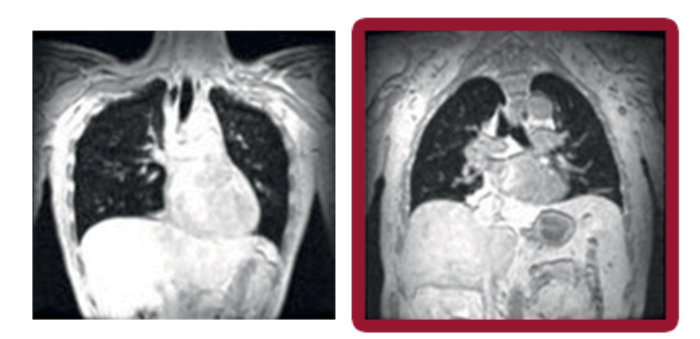

En un estudio de historia natural, los pacientes con LOPD tenían deficiencias significativas en la expansión de los pulmones durante la inspiración en comparación con los voluntarios sanos (P = 0,001)

Las reducciones en el volumen inspiratorio máximo tienen un impacto directo y negativo en la función respiratoria al limitar la capacidad vital forzada (CVF)

Pulmones sanos Enfermedad de Pompe

Volumen inspiratorio máximo

Las imágenes coronales de resonancia magnética evaluaron los movimientos máximos de final de inspiración y final de espiración mientras los sujetos contenían la respiración durante 12 segundos. El volumen pulmonar (representado en negro) en cada sujeto se calculó fuera de línea y se normalizó por la proporción de la longitud del pulmón en la inspiración dividida por la longitud en la espiración.